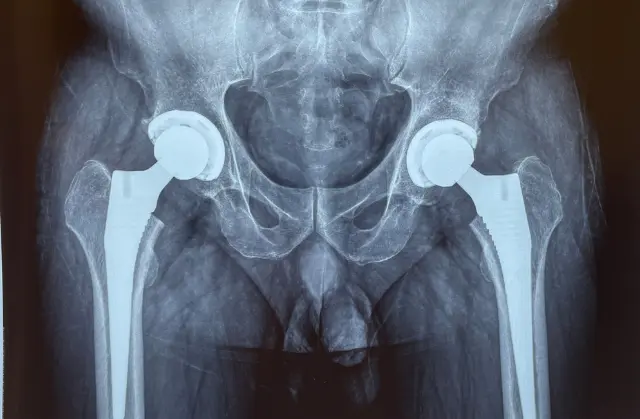

Meet Your Surgeon Dr. Shreyas Zalariya is a highly distinguished Orthopedic Consultant and Joint Replacement & Arthroscopy Surgeon. Having undergone rigorous Australian training, he combines international surgical standards with a compassionate, patient-first approach.

With advanced fellowship training from Australia, Dr. Shreyas Zalariya brings a global standard of orthopedic excellence to every patient. He specializes in cutting-edge, minimally invasive surgical techniques designed to minimize tissue damage and accelerate your return to an active life. Whether it is a complex joint replacement or a sports-related arthroscopy, Dr. Zalariya’s approach combines clinical precision with a deep commitment to long-term patient mobility and wellness.